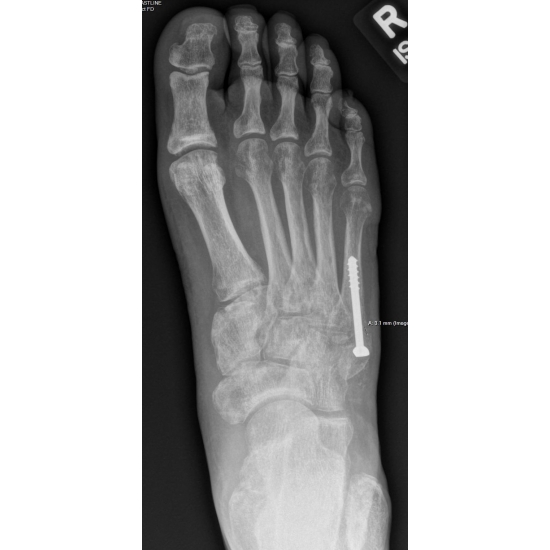

2. Zone 1 fifth metatarsal fracture, non-union

Because the athlete was frustrated with the limited improvement after four months of immobilization, she and the surgeon proceeded with an open reduction internal fixation of the fifth metatarsal fracture with bone autograft from the calcaneus. Case Photo #10

This case highlights a Zone 1 fifth metatarsal fracture complicated by non-union. Even with a confirmed fracture, inversion and plantarflexion injuries can also result in concurrent ligament sprains, peroneal tendon injuries, or other occult fractures, such as to the cuboid or calcaneus. Therefore, it is important to include ligament stability testing during the clinical exam. The proximal fifth metatarsal receives blood from branches of the lateral plantar artery proximally and the nutrient artery distally, with a relative "watershed" area at the metaphyseal-diaphyseal junction. This helps to explain why Zone 1 fractures generally heal more reliably than those fractures seen in Zone 2 and Zone 3, which traverse this watershed area, resulting in a higher risk for delayed union or non-union. With regards to imaging considerations, serial x-rays are a cost-effective way to assess and follow callus formation and fracture gap changes. CT can help confirm a fracture gap or sclerosis suggesting non-union, and it is also valuable for preoperative planning. Surgical indications for Zone 1 fractures may include displacement greater than 3 mm, rotational malalignment, symptomatic non-union, the presence of concomitant injuries that limit effective immobilization, or a high-level athlete needing predictable union for timely return to sport. In the presence of sclerotic edges or non-union, the calcaneus is a common donor site used for a graft due to its proximity, as well as its composition of cancellous bone, which provides a high osteogenic potential. As with other injuries, clear and realistic expectations are essential for athlete satisfaction and adherence. Proper rehabilitation and a gradual return to sport protocol may help to reduce the risk of re-injury. Prolonged immobilization and delayed healing can affect the mental health of athletes. In some athletes, a biomechanical assessment can be considered to address factors that may predispose to re-injury.